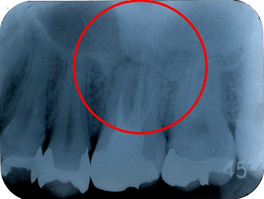

左上第一大臼歯部デンタルレントゲン(初診時)

歯の神経の治療(根管治療)が適切に行われておらず、

問題があることがうかがえました。